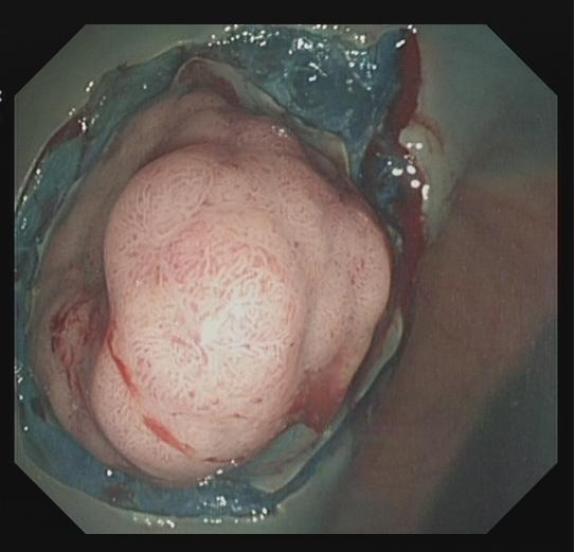

■ IIa-c型病变

对于直径较大的IIa-c型病变及部分Is病变,若直接圈套切除,可能造成全层损伤,通过黏膜下注射液体可增加病变隆起高度,减少圈套和切除难度。而术中是否具备隆起症,又是确定腺瘤良恶性和有无内镜下治疗指征的一个重要依据。此方法能增加直径<2 cm 腺瘤的完整切除率。

上下滑动查看△图4 Ⅱa 型息肉 EMR 治疗流程图。